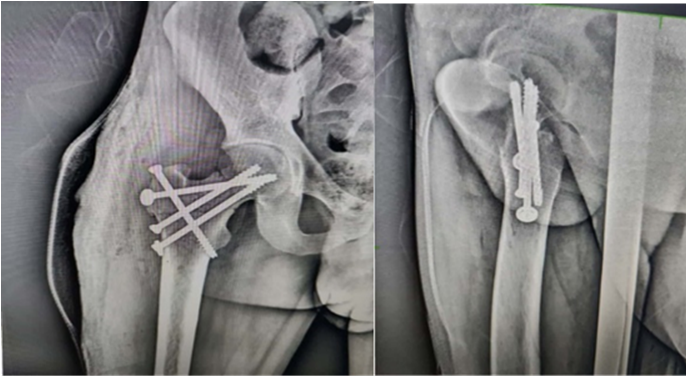

Initially, two parallel guide wires for 6.5 mm CC screws were passed to stabilize the femoral neck fracture. This was followed by one guide wire fixing the GT to the femoral head and another guide wire from the tip of GT directed toward the lesser trochanter. The femoral neck screws were passed first and compression was achieved across the fracture site. Then, the screws fixing the GT fragment were passed. Care was taken to ensure that all the screw threads crossed the fracture lines. Due to the complexity of the fracture pattern, we delayed post-operative mobilization. Non-weight-bearing walking with axillary crutches was started at 6 weeks, progressing to full weight-bearing once radiological union at the fracture site was confirmed at 12 weeks postoperatively (Fig. 3 and 4).

Figure 3: – Immediate post-operative X-rays.